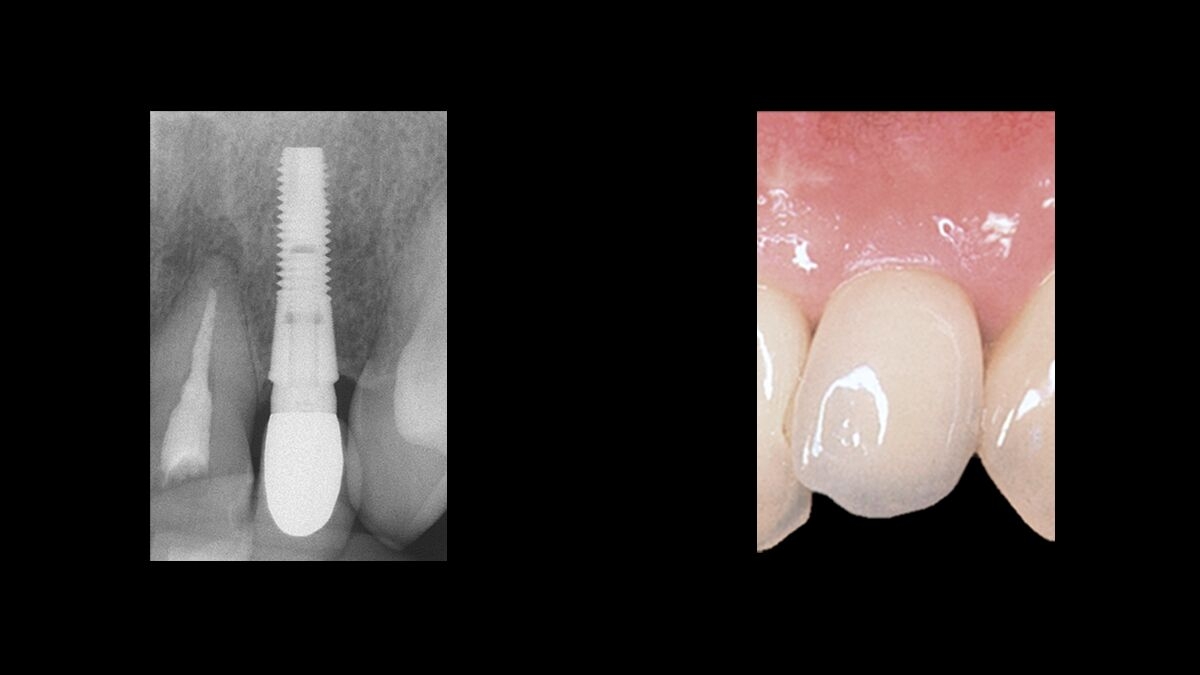

Superb function. Great esthetics.

The maintenance of marginal bone is the foundation for dental implant success and a key factor for the esthetic outcome.

When working with Astra Tech Implant System EV the unparalleled marginal bone maintenance helps you deliver:

Natural esthetics

— the liberty to happily show a beautiful smile and enjoy life to the fullest.